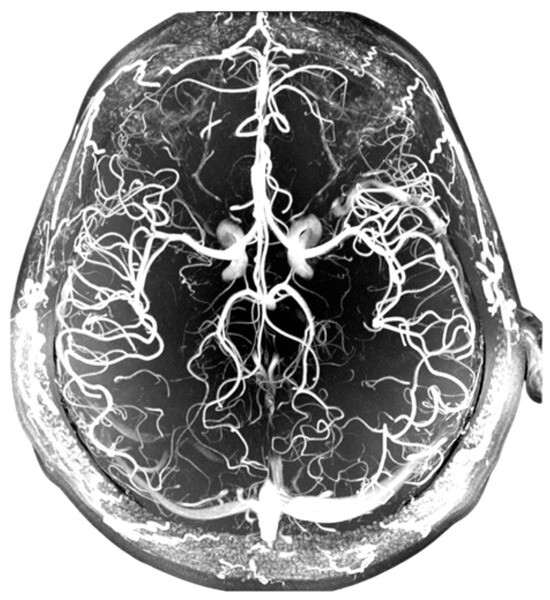

- Aziz, A.A.; Izhar, L.I.; Asirvadam, V.S.; Tang, T.B.; Ajam, A.; Omar, Z.; Muda, S. Detection of Collaterals from Cone-Beam CT Images in Stroke. Sensors 2021, 21, 8099. [Google Scholar] [CrossRef]